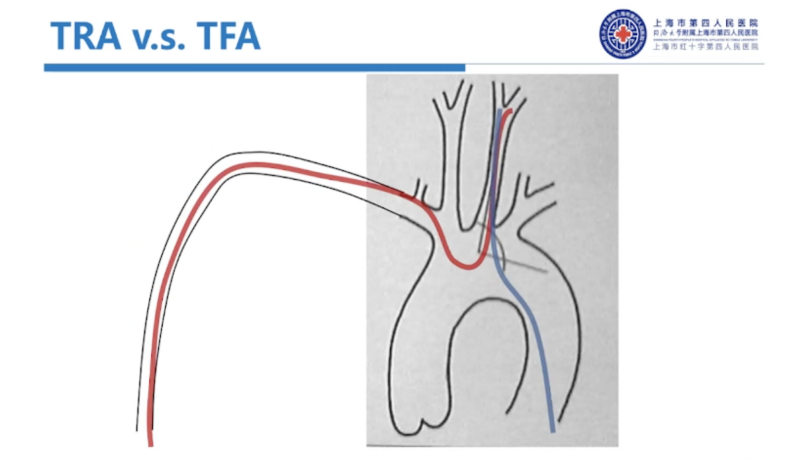

经股入路并发症率高,总发生率约2%-8%(神经介入前瞻性研究数据),且一些严重的股动脉入路并发症甚至可致死致残,如后腹膜血肿、假性动脉瘤、股动静脉瘘、股动脉闭塞等。

相较股动脉入路,经桡入路更安全,并发症发生率更低,筋膜间隙综合征为0.1%左右,RA闭塞<1%;RA痉挛5%-10%,全因致死、致残率较经股入路降低60%(冠脉),同时,对病人来说,术后舒适度更高,术后无需强制平卧(避免腰背疼痛、诱发心衰、下肢静脉血栓等),可即刻站立活动(更方便,自行如厕等)。

经桡和经股最大的区别:经桡入路,神经介入治疗存在右锁骨下动脉到颈内动脉的反向弯,普通经股入路的导管难以通过,存在打折风险,需要用Sim头端的造影导管进行超选。